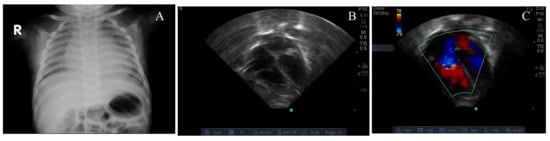

| Peak estimate of RVSP (mm Hg) | 82 | 74 | 60 | 67 |

| Resolution of PH by echocardiogram after thiamine | Improvement started by 4 h, resolution by 5 days. | Improvement by 3 h, resolution by 6 days. | Improvement started by 8 h, resolution by 7 days. | Resolution 5 days. |